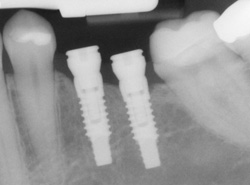

Implants

If you have missing teeth, it is crucial to replace them. Without all your teeth, chewing and eating can destabilize your bite and cause you discomfort. When teeth are missing, your mouth can shift and even cause your face to look older. Implants are a great way to replace your missing teeth.

An implant is a new tooth made of steel and porcelain that looks just like your natural tooth. Your implant is composed of two parts that mimic a tooth's root and crown. The implant's "root" is a titanium steel rod placed into the jaw bone to act as a root. Once the rod is in place, a porcelain crown is attached to replace the top part of your tooth.

Implants may also be used to anchor dentures, especially lower dentures that tend to shift when you talk or chew. Plus, for patients with removable partial dentures, implants can replace missing teeth so that you have a more natural-looking smile.